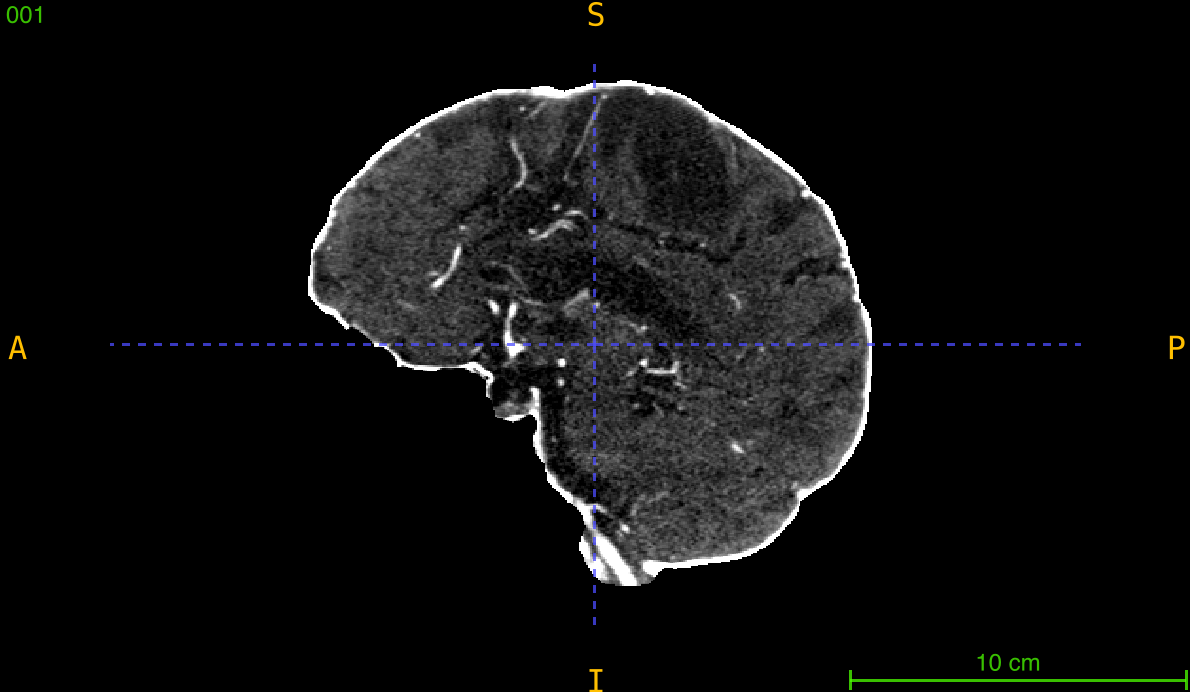

Comparing Interpolation Quality

Visualize resampling results:

import nibabel as nib

import matplotlib.pyplot as plt

from nidataset.preprocessing import resampling

# Resample

resampling(

nii_path="visualization/scan.nii.gz",

output_path="visualization/resampled/",

desired_volume=(224, 224, 128),

debug=True

)

# Load and compare

original = nib.load("visualization/scan.nii.gz")

resampled = nib.load("visualization/resampled/scan_resampled.nii.gz")

orig_data = original.get_fdata()

resamp_data = resampled.get_fdata()

# Extract middle slices

orig_mid = orig_data.shape[2] // 2

resamp_mid = resamp_data.shape[2] // 2

fig, axes = plt.subplots(1, 2, figsize=(12, 5))

axes[0].imshow(orig_data[:, :, orig_mid], cmap='gray')

axes[0].set_title(f'Original ({orig_data.shape})')

axes[0].axis('off')

axes[1].imshow(resamp_data[:, :, resamp_mid], cmap='gray')

axes[1].set_title(f'Resampled ({resamp_data.shape})')

axes[1].axis('off')

plt.tight_layout()

plt.savefig('resampling_comparison.png', dpi=150)

print("Comparison saved: resampling_comparison.png")